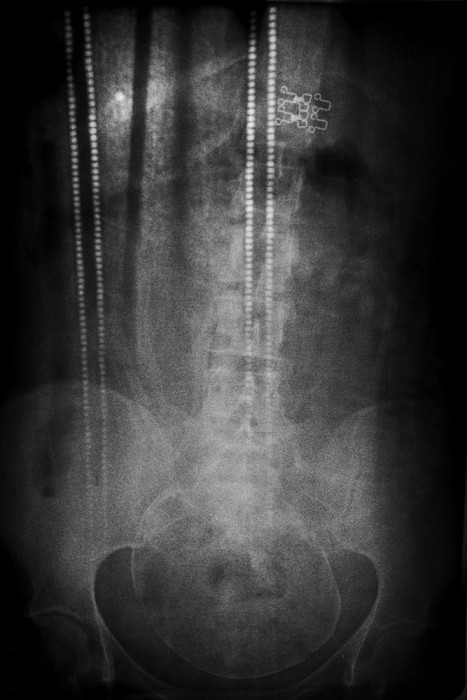

© Tuane Eggers, Symbiogenesis, Porto Alegre/RS, Brazi